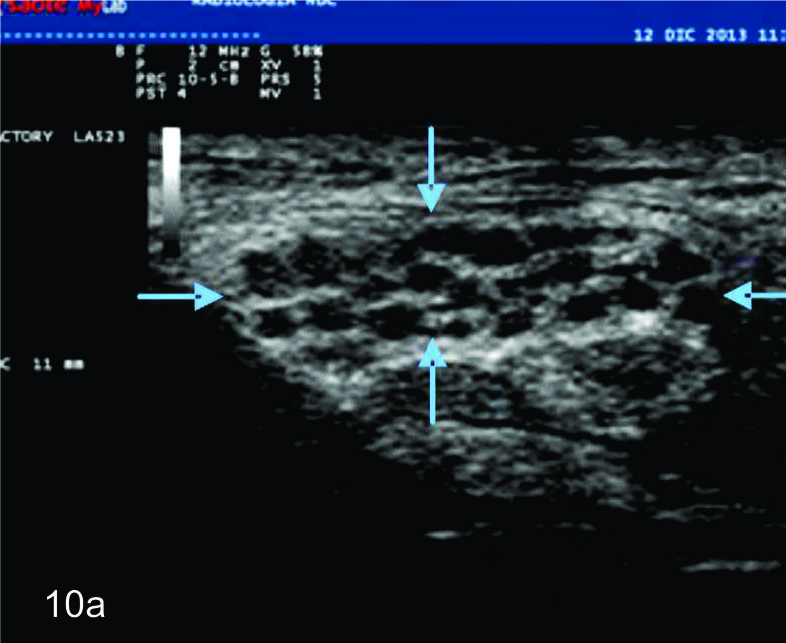

Dada las características ultrasonográficas normales de los nervios, algunas variantes anatómicas pueden ser reconocidas por este método. Entre ellas la bifurcación proximal del mediano en el puño es una de las más frecuentes. De manera similar algunas anomalías heredables y del desarrollo del sistema nervioso periférico, como el agrandamiento fusiforme del nervio mediano por tejido fibroadiposo (denominado hamartoma fibrolipomatoso (Fig.10), la hipertrofia de los nervios en el síndrome de Charcot-Marie-Tooth y el aumento de los nervios en la neuropatía hereditaria secundaria a parálisis por compresiones pueden ser reconocidas por ultrasonido. En estas enfermedades, los hallazgos ultrasonográficos pueden contribuir a la comprensión de la fisiopatología demostrando de forma no invasiva algunos hallazgos morfológicos de interés (1).

Figura 10

Hamartoma fibrolipomatoso del nervio mediano

A y B, cortes transversales en antebrazo y puño, las flechas azules señalan al nervio mediano aumentado de tamaño con fascículos engrosados. C- Corte longitudinal con hallazgos similares en plano longitudinal del nervio (flechas azules).